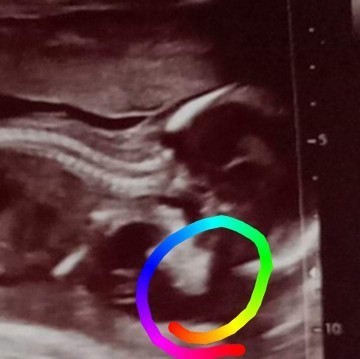

17Week ตรงนี้ใช่สันจมูกน้องมั้ยคะ หรือต้องรอให้อายุครรภ์เยอะกว่านี้ก่อนถึงจะดูออก

ของเราซาวด์ตอนอายุครรภ์18วีค ดูเหมือนโด่งนะคะไม่รู้ว่าแสงมันสะท้อนหรือว่ายังไงแต่ตัวเราเองก็โด่งเพราะกรรมพันธุ์ค่ะตัวแฟนเองก็มีโด่งหน่อย 😅

บ้านนี้เห็นชัดตอน 24w ค่ะ หมอทักว่าโด่งมาเลย